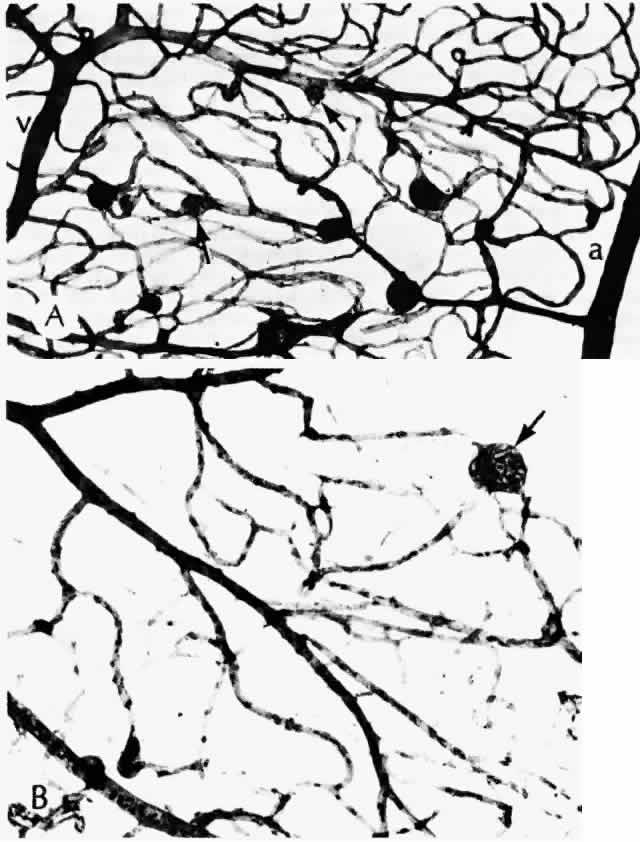

As shown by trypsin digestion, capillary pericytes are lost first,27 followed by endothelial cells (Figs. 6 and 7). Aldose reductase, one of the enzymes in the sorbitol metabolic pathway, is present in significant quantities in retinal capillary pericytes, but not in endothelial cells, and may thus be implicated in the formation of microaneurysms.37 The final result is an acellular segment of capillary that is nonperfused on fluorescein angiography.36

Fig. 6. Diabetic retinal capillary. A. Basement membrane shell (arrows) is the only remaining indication of where the pericytes had been. B. Nondiabetic normal capillary shows the basement membrane shell (arrow) around the pericyte. C. Diabetic capillary has only a basement membrane shell (arrow), with the nucleus absent. (A, PAS, × 630; B, PAS, × 850; C, PAS, × 630)

Fig. 7. Retinal capillary microaneurysm (RCM). A. RCMs occur in random distribution between the arteriole (a) and venule (v). “Young” RCMs are seen as saccular capillary outpouchings with proliferated endothelial cells (arrows). “Old” RCMs appear as solid black balls with their lumens obliterated by PAS-positive material. Note the darker color of the capillaries with thickened basement membranes and arteriolar-venular connections. B. Very large RCM (arrow) or the tiny hemorrhages associated with abnormal vessels are probably responsible for the RCMs seen clinically. (A, PAS, × 40; B, PAS, × 115)